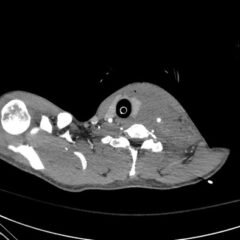

Each day, novel information is being learned about Coronavirus disease 19 (COVID-19), a disease increasingly seen in the emergency department (ED). Our case adds to reports of a maculopapular rash among the newer symptoms to be aware of in diagnosing COVID-19. A 35-year-old male presented with an 11-day history of fever, dry cough, diarrhea, and change in taste. He endorsed two known exposures to COVID-19 and had previously tested negative twice for the virus. The patient additionally complained of a whole-body, pruritic rash that presented six days after his initial symptoms. A workup was completed for the patient’s fever and labs only revealed a potassium of 3.3 mEq/L. A chest X-ray showed right basilar patchy opacities consistent with pneumonia, and the patient tested positive for COVID-19 and negative for Epstein-Barr Virus, a commonly missed culprit in those with a rash, via polymerase chain reaction (PCR). The patient’s vitals were stable, and he was discharged with supportive measures at home. COVID-19 was determined as a likely etiology for the rash. With new insights into COVID-19 every day, we demonstrate a case of viral exanthema as a potential presenting manifestation in a COVID-19 patient and one that medical providers should be familiar with in these patients in the ED.